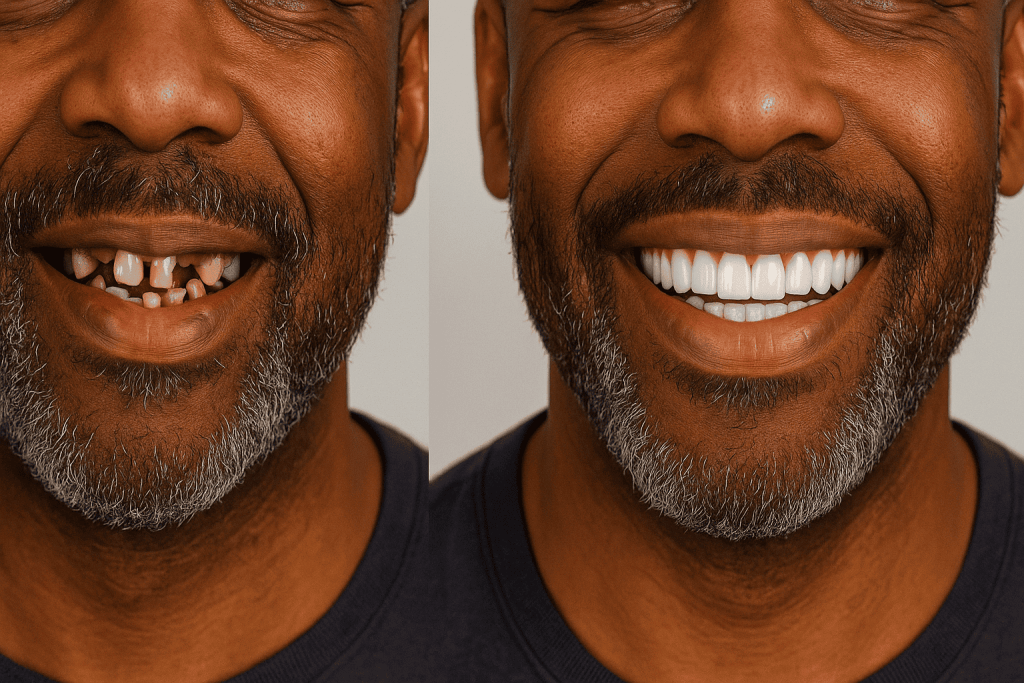

Prima e dopo impianti dentali in Turchia

Le foto prima e dopo mostrano in modo concreto le trasformazioni possibili e completano le recensioni sugli impianti dentali in Turchia. Questi interventi offrono una soluzione affidabile per sostituire i denti mancanti, migliorare l’estetica del sorriso e ritrovare una masticazione confortevole e naturale.

L’evoluzione dei risultati conferma l’affidabilità di questo trattamento, come dimostrano le numerose recensioni sugli impianti dentali in Turchia. I pazienti sottolineano sia il miglioramento estetico, sia la solidità ritrovata e il netto aumento della qualità di vita dopo l’intervento.